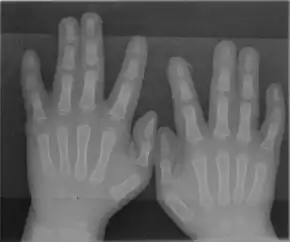

Hands with partial syndactyly – fusion of two fingers

Andersen–Tawil syndrome is generally diagnosed based on symptoms, the findings on examination, and the results of an electrocardiogram.[4] Clinical diagnostic criteria have been proposed which suggest that a diagnosis can be made if two of the following four criteria are met: (1) periodic paralysis; (2) ventricular arrhythmias (frequent ventricular ectopic beats or ventricular tachycardia), a prolonged QT interval when corrected for rate, and/or a prominent U wave; (3) at least two of the following dysmorphic features: low-set ears, wide-set eyes, a small mandible, fifth-digit clinodactyly, and syndactyly; and (4) a family member with confirmed Andersen–Tawil syndrome.[4]